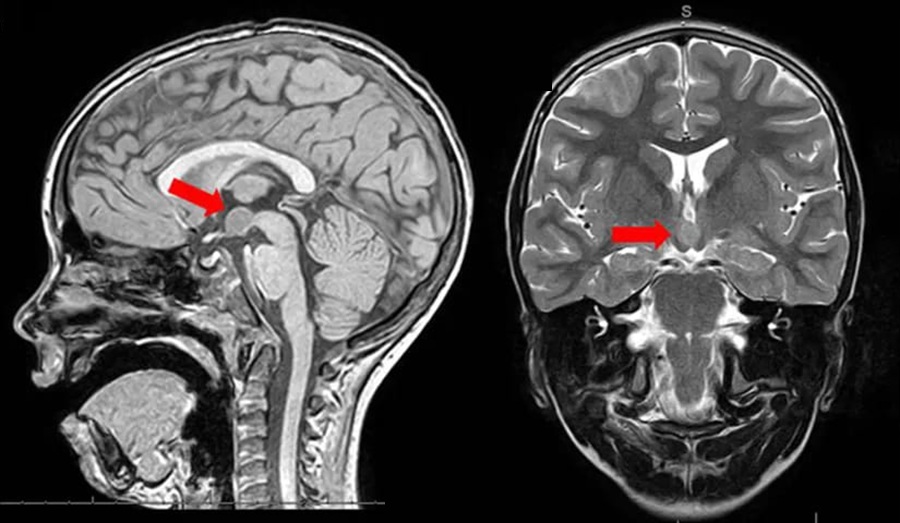

Магнитно-резонансная томография гипофиза – это метод, который позволяет с высокой точностью визуализировать анатомию железы, прилегающих тканей и окружающих структур. На снимках хорошо различимы очертания, его симметричность, однородность, толщина ножки, а также наличие даже минимальных изменений, таких как микроаденомы, кисты, воспалительные участки или следы перенесённых травм. Особенно важным преимуществом является возможность оценки взаимодействия опухолевых или воспалительных процессов с близлежащими структурами – зрительными нервами, гипоталамусом, стенками турецкого седла.

Технология позволяет выявить очаги, которые ещё не вызывают выраженных симптомов, но уже начали нарушать функцию железы. С её помощью диагностируются как гормонально неактивные образования, так и опухоли, вырабатывающие избыток пролактина, гормона роста или адренокортикотропного гормона. Кроме того, при помощи контрастного усиления можно чётко определить границы новообразований, их сосудистую активность и степень прорастания в окружающие ткани. Это особенно важно при планировании хирургического вмешательства или при оценке динамики после проведённого лечения.

Полученные изображения анализируются врачом-рентгенологом, имеющим опыт в нейрорадиологии. Он оценивает размеры гипофиза, его форму, контуры, плотность ткани, однородность сигнала, наличие очагов, уплотнений, кист или опухолей. Внимание также уделяется состоянию ножки железы, симметрии расположения, изменениям в турецком седле и степени давления на окружающие структуры, включая зрительный перекрёст. При необходимости в заключении указывается предполагаемая природа выявленного образования и даются рекомендации по дальнейшему обследованию.

МРТ гипофиза позволяет обнаружить широкий спектр отклонений, часть из которых может протекать бессимптомно на ранних стадиях. Одной из наиболее частых находок становятся аденомы – доброкачественные опухоли, которые подразделяются на микроаденомы (до 10 мм) и макроаденомы (свыше 10 мм). Некоторые из них активно вырабатывают гормоны, приводя к таким состояниям, как пролактинома, акромегалия или болезнь Иценко-Кушинга. Другие не продуцируют гормоны, но могут оказывать давление на зрительные пути и другие структуры мозга.

Помимо аденом, на снимках нередко выявляются кисты, врождённые аномалии строения, участки воспаления или последствия перенесённых травм. Иногда фиксируются изменения в турецком седле, расширение гипофизарной ножки или признаки компрессии зрительного перекрёста. В ряде случаев томограмма обнаруживает отдалённые признаки метастатических процессов, затрагивающих область железы. Также возможна визуализация пустого турецкого седла – анатомической особенности, при которой гипофиз выглядит уменьшенным или сдавленным, что требует исключения функциональных нарушений.